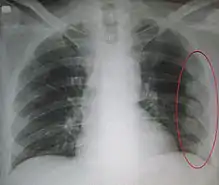

معرض صور